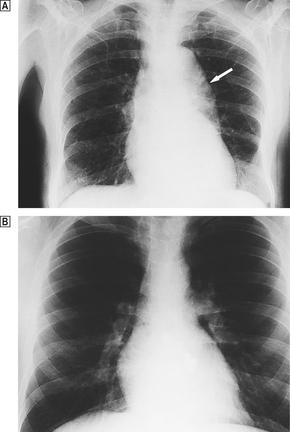

The net effect of these changes is to reduce both the strength and the elasticity of the vessel wall. Progressive dilatation is a common ageing phenomenon in both the aorta and the coronary arteries. In the ascending aorta this can lead to stretching of the aortic valve ring and aortic incompetence. Dilatation of the arch and thoracic aorta produces the characteristic ‘unfolding’ seen in chest X-rays (Fig. 13.2).

image

Fig. 13.2 Unfolding of the aorta. image There is a prominent bulge (arrow) caused by dilatation of the arch and descending aorta. If the dilatation involves the aortic valve ring, aortic incompetence may result. image Normal X-ray for comparison.